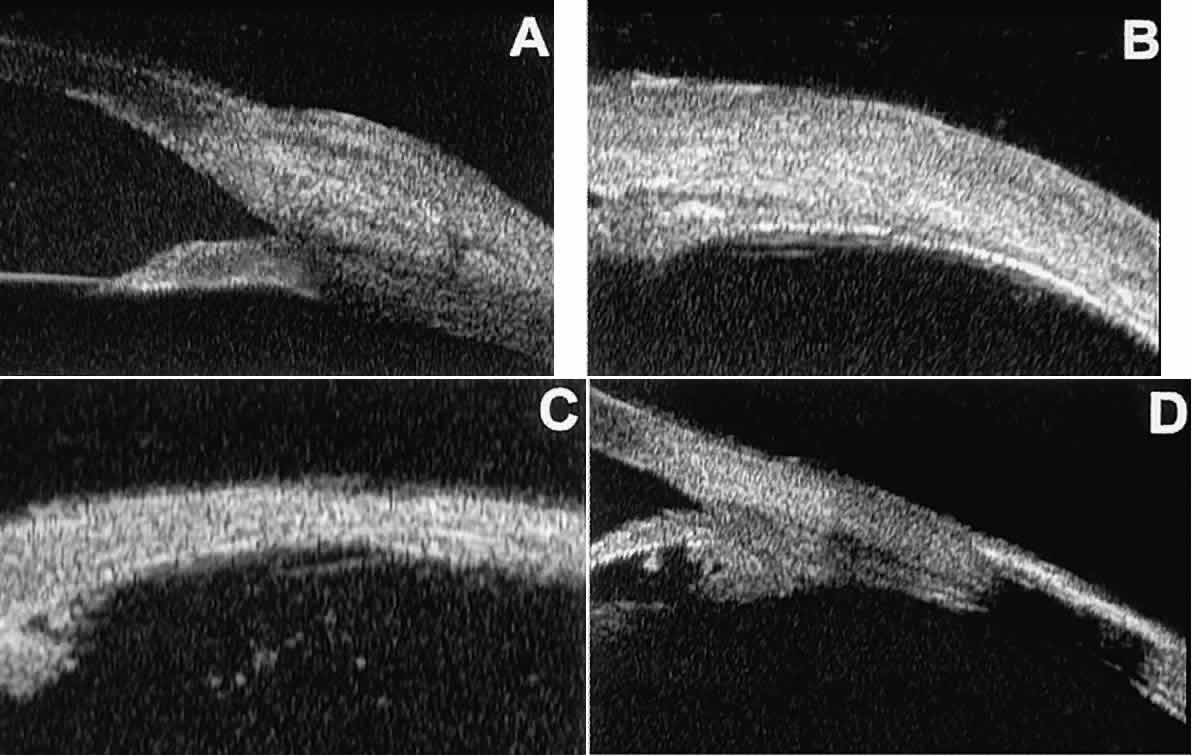

In open-angle glaucoma, UBM can be used to measure the anterior chamber angle in degrees, to assess the configuration of the peripheral iris, and to evaluate the trabecular meshwork (Fig. 9).2,4 The angle configuration can be graded and compared with gonioscopic findings. In certain patients with open-angle glaucoma, UBM can provide information that may be of some diagnostic value (Fig. 10). For example, in pigment dispersion syndrome (see Fig. 10A),6 UBM typically reveals posterior bowing of the peripheral iris (“q” configuration of peripheral iris by Spaeth classification5). In plateau iris syndrome (see Fig. 10B),7 UBM usually reveals abnormally steep anterior angulation of the peripheral iris (“s”configuration of peripheral iris by Spaeth classification5), insertion of the iris from the anterior ciliary body, and retroiridic projection of the ciliary processes. In eyes with peripheral anterior synechiae (see Fig. 10C and D), UBM can reveal the extent of iridocorneal adhesion even if the cornea is hazy or opaque.

Fig. 10. UBM features of special glaucoma cases. A. Pigment dispersion syndrome with posterior bowing of peripheral iris (“q” configuration by Spaeth gonioscopic grading system). B. Plateau iris syndrome with origin of iris from anterior surface of ciliary processes behind peripheral iris, slitlike narrowing of peripheral angle, and abrupt transition from steep peripheral iris to flat iris midzone. C. Broad peripheral anterior synechia with posterior bowing of nonadherent iris. D. Peripheral anterior synechia with aqueous-filled slit between site of iridocorneal adhesion and iris root after cataract extraction with implantation of posterior-chamber IOL.